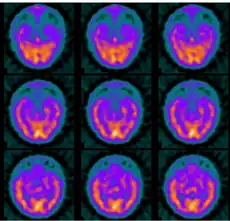

| Brain SPECT transaxial images of a patient afflicted with Hashimoto's encephalopathy. | |